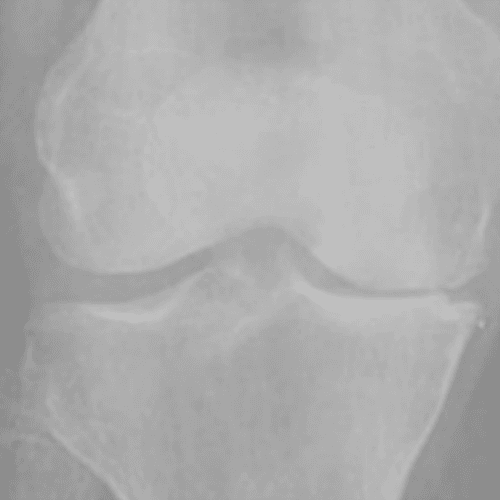

Kellgren and lawrence (KL) Grading System

통증이 발생한 무릎을 x-ray로 촬용한 관절염 결과를 총 4단계로 구분한 것을 KL Grading System 이라고 부르며

2~3단계의 환자들에게 무릎 연골 줄기세포 시술을 진행합니다.

Grade 3

연골이 많이 손상되어 골극이 심해짐

Grade 4

연골이 거의 사라지고 골극이 매우 심해짐